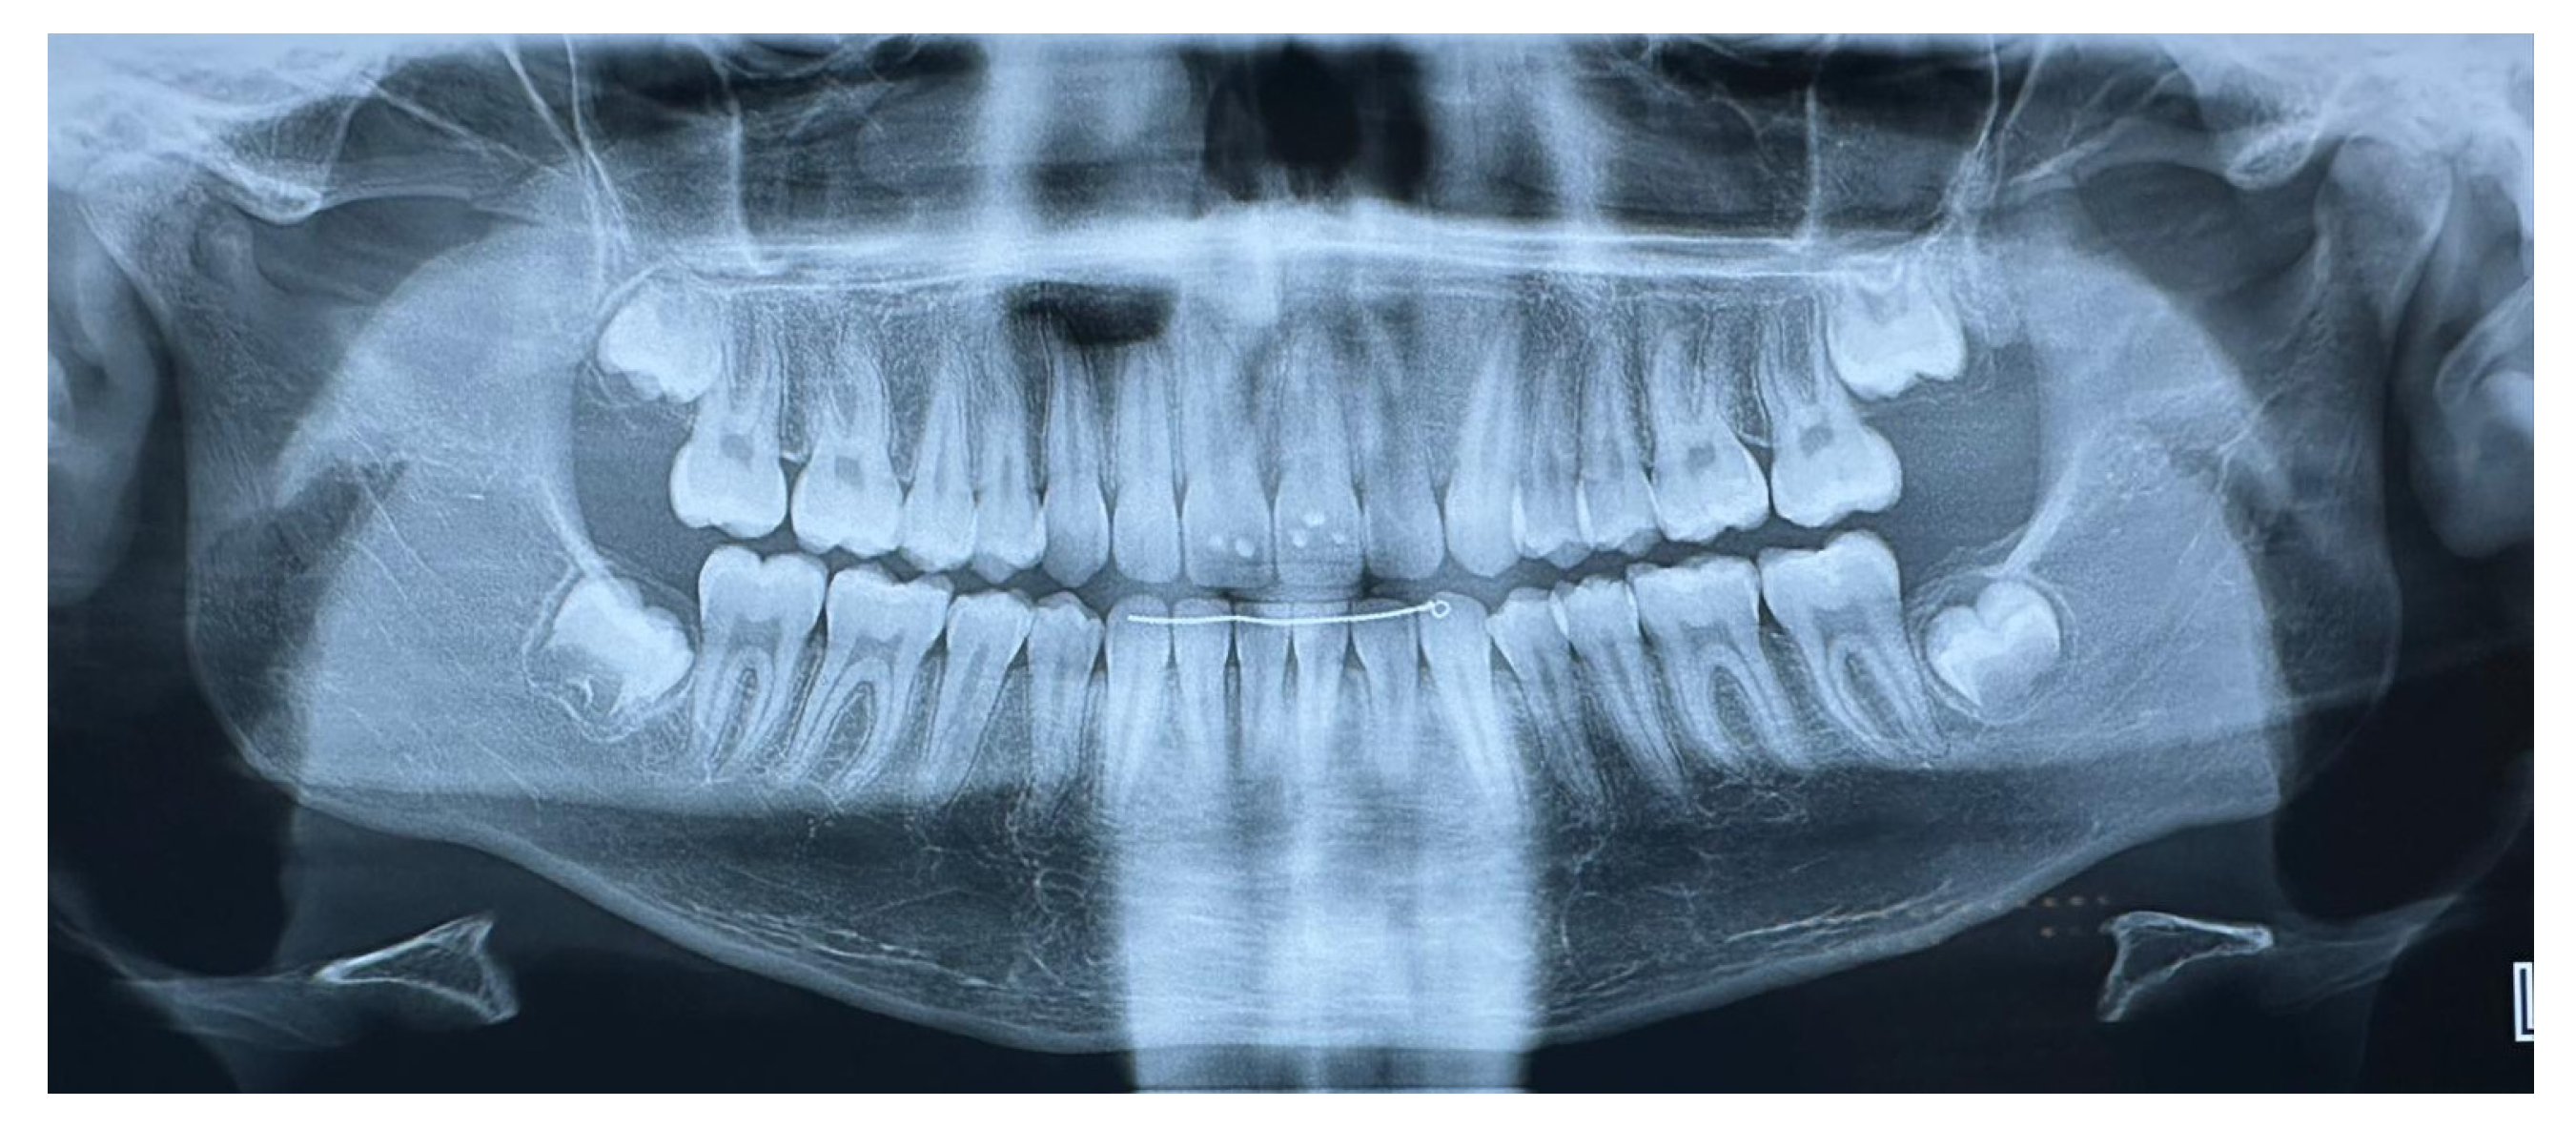

2.2. Case Report Throughout Clinical Phases

3. Results